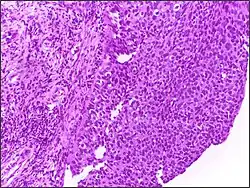

![]() |

Tumor giant cell | Malignant neoplasm showing marked anaplasia. Note the marked nuclear pleomorphism, bizarre cells and tumor giant cells. | Category: Histopathology of giant cell tumors | Giant cell tumor |